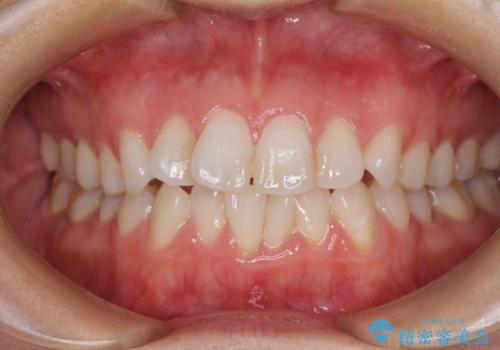

長年気にしていた前歯 インビザラインで目立たず改善

- ワイヤーではない矯正治療があると聞いたとのことで来院された患者様です。

長年前歯のデコボコを気にしていたもののワイヤー矯正に抵抗があり躊躇していたそうですが、インビザラインなら治療してみたいとのことで相談にいらっしゃいました。

インビザライン適用の歯列であったため、歯と歯の間を削るIPRを用いて改善することとしました。